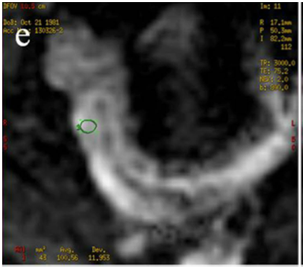

Figure 3 Receiver operating characteristic (ROC) curves illustrating the performances of the apparent diffusion coefficient (ADC), the quantitative parameter of Diffusion-Weighted Magnetic Resonance to predict a post operative recurrence Rutgeerts’ score > i2

ADC ≤ 1,82 x 10-3 mm2/s

Sensibilità 88,9% (51,8 – 99,7; CI 95%)

Specificità 83,3% (35,9 – 99,6; CI 95%)

Rutgeerts’score > i2

The search for an ADC value to be used as cut-off for the presence of post-operative recurrence of degree i3 or i4 was conducted through the analysis of ROC curves, highlighting that a value of ADC ≤ 1.82 x 10-3 mm²/s could predict recurrence of degree >i2 with a sensitivity of 88.9% (51.8 to 99.7, CI 95%) and a speci-ficity of 83.3% (35.9 to 99.6, CI 95%), (Figure 3).

Such subdivision, through the analysis of Receiver-Operating Characteristic (ROC) curves, allowed to calculate an ADC cut-off, equal to 1.82 x 10ˉ³ mm²/s, with a sensitivity of 88,9% (from 51.8 to 99.7, CI 95%) and a specificity of 83.3% (from 35.9 to 99.6, CI 95%) able to predict, for lower values, a post-operative relapse Rs> i2. This result seems to us very important since the presence of a diffuse aphthous ileitis with diffusely inflamed mucosa, equal to a Rutgeerts’ score i3, represents a significant landmark in the clinical management of CD patients, because it requires an intensification of medical therapy.